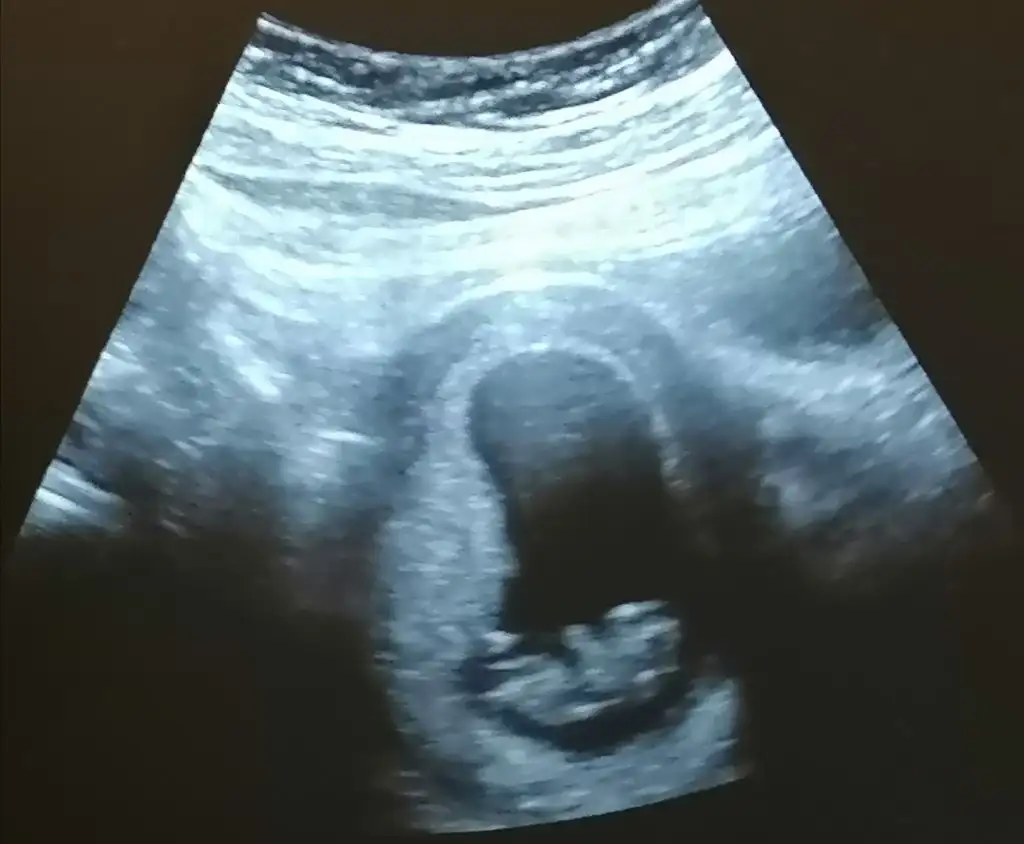

Buda bizim minnoş ama 9 haftalık burda aslında fasülye gibi olmadı 10. 12.haftalarda belli oluyor şuan değilOyy yine de baya gelişmiş benim ilk ultrason 6+5 te verildi ve bildiğiniz bir tektaş yüzüğe benziyorduşuan 8. Haftada böyle görünmesi benim için baya farklı geldi Maşallah ya mucizeler resmen

Oyyyy 9 haftalık mııBuda bizim minnoş ama 9 haftalık burda aslında fasülye gibi olmadı 10. 12.haftalarda belli oluyor şuan değil

Oyyyy 9 haftalık mııama ya nasıl nasıl bu kadsr çabuk bebek gibi görünüyorlar allahım resmen mucize ya mucize ❤ Nasıl hızlı gelişiyorlar maşallah miniğe Eki Görüntüle 2664141